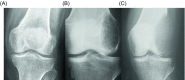

Giant cell tumor (GCT) of bone is a locally aggressive benign neoplasm that is associated with a large biological spectrum ranging from latent benign to highly recurrent and occasionally metastatic malignant bone tumor. It accounts for 4-10% of all bone tumors and typically affects the meta-epiphyseal region of long bones of young adults. The most common site involved is the distal femur, followed by the distal radius, sacrum, and proximal humerus. Clinical symptoms are nonspecific and may include local pain, swelling, and limited range of motion of the adjacent joint. Radiographs and contrast-enhanced magnetic resonance imaging (MRI) are the imaging modalities of choice for diagnosis. Surgical treatment with curettage is the optimal treatment for local tumor control. A favorable clinical outcome is expected when the tumor is excised to tumor-free margins, however, for periarticular lesions this is usually accompanied with a suboptimal functional outcome. Local adjuvants have been used for improved curettage, in addition to systematic agents such as denosumab, bisphosphonates, or interferon alpha. This article aims to discuss the clinicopathological features, diagnosis, and treatments for GCT of bone.